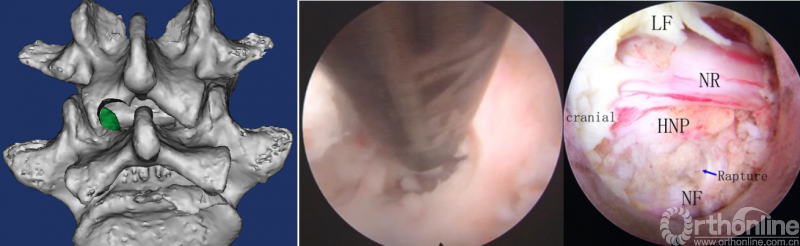

第一步“定”:X线定位在上位椎体下关节突下三分之一部;

第二步“辨”:镜下辨别下关节突关节囊;

第三步“凿”:凿除部分下关节突,显露上关节突及黄韧带;

第四步“分”:分离上关节突及黄韧带;

第五步“咬”:咬除部分上关节突,显露椎间盘及神经根;